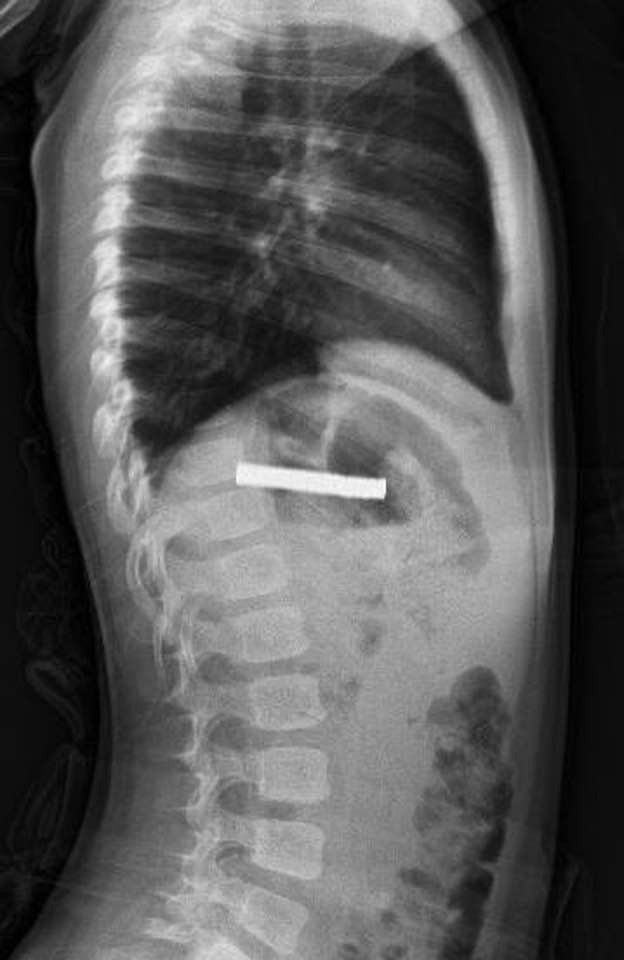

Endoskopik yöntemle 19 mıknatıs çıkarıldı

Fırat Üniversitesi Çocuk Gastroenteroloji, Hepatoloji ve Beslenme Bilim Dalı Başkanı Prof. Dr. Yaşar Doğan, çocuğun yemek borusuna yapışmış 19 mıknatısı endoskopik yöntemle başarılı bir şekilde çıkardı. Doktor Doğan, operasyonun titizlikle yürütüldüğünü belirtti.

Mıknatısların uzun süre yemek borusunda kalması nedeniyle, çocuğun yemek borusu ve mide girişinde zedelenme meydana geldi. Erken müdahale sayesinde daha ciddi komplikasyonların önüne geçildi.